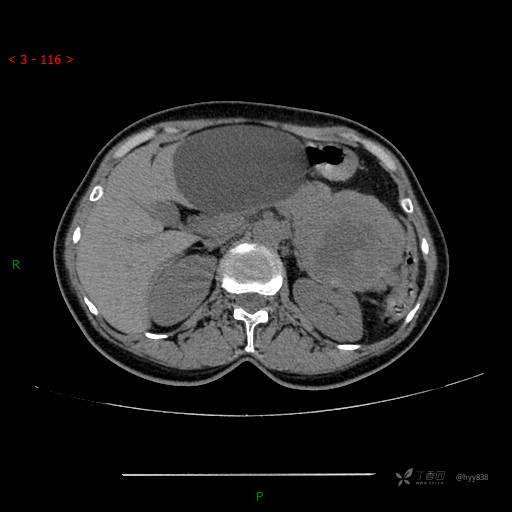

增强动脉期